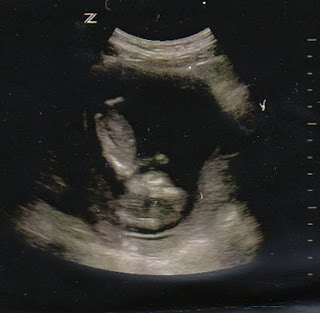

Baby Miller's First Photoshoot

This weekend we visited the bay area...and while down my sister decided that she was still not convinced that I am only carrying one baby. Here in Mt. Shasta I only get one ultrasound - at 20 weeks...and she couldn't wait.

One of the perks of being a labor and delivery nurse is that she was able to ask a midwife that she works with to "scan" me and check. So, on Friday night at 10:30 Julie and her hubby, Reece & I went in and had an ultrasound done.

There is only one baby...one adorable baby :) Hopefully we'll be able to find out if it is a boy or girl at the end of May/beginning of June.